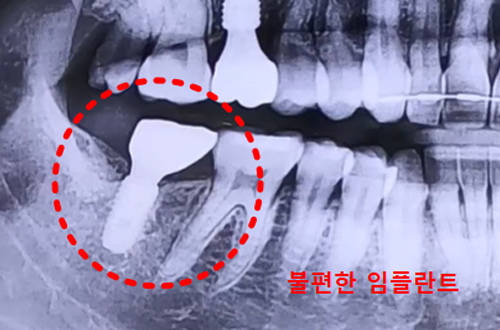

엑스레이 상으로는 별다른 문제가 발견되지 않았고 임플란트 역시

반듯하게 잘 심어져 있었는데, 정밀 검사를 해 보니

임플란트가 한쪽으로 치우쳐서 식립된 것을 확인할 수 있었습니다.

CT 촬영에서 기울어진 형태의 치조골에, 기울어진 각도와 맞지 않게

임플란트가 식립이 된 것이 보였고 이 때문에 잇몸에 염증이 생겼던 것이죠.